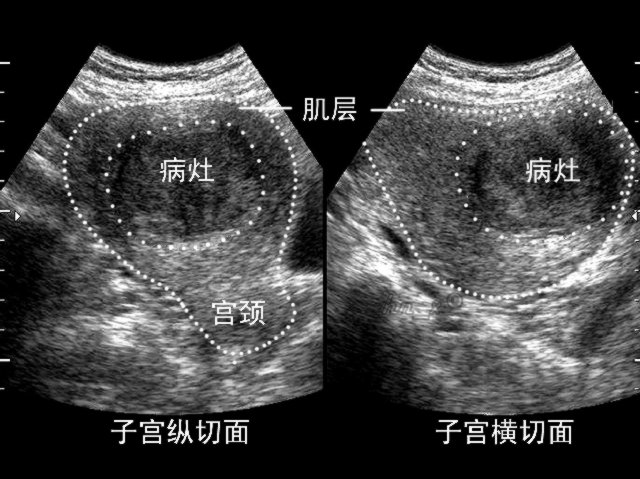

子宫肉瘤患者体征:子宫增大,外形不规则;宫颈口有息肉或肌瘤样肿块,呈紫红色,极易出血;继发感染后有坏死及脓性分泌物。晚期肉瘤可累及盆侧壁,子宫固定不活动,可转移至肠管及腹腔,但腹水少见。

因子宫肉瘤临床表现于子宫肌瘤及其他恶性肿瘤相似,术前诊断较困难。对绝经后妇女及幼女的宫颈赘生物、迅速长大伴疼痛的子宫肌瘤均应考虑有无肉瘤可能。辅助诊断可选用阴道彩色脉冲多普勒超声检查,诊断性刮宫等。确诊依据为组织病理学检查。如有疑问可拨打热线电话:0755-82338559 。